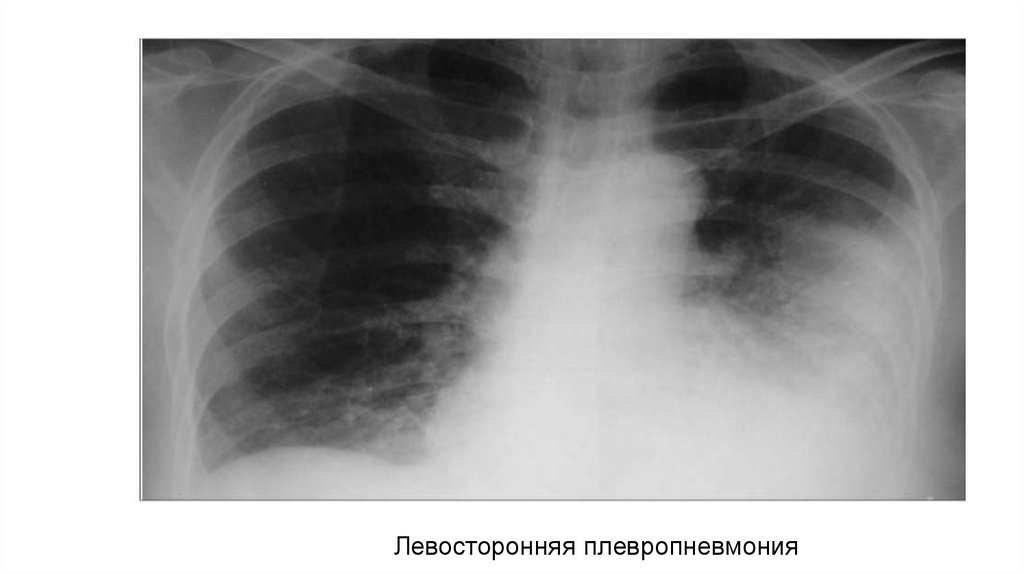

Левосторонняя плевропневмония